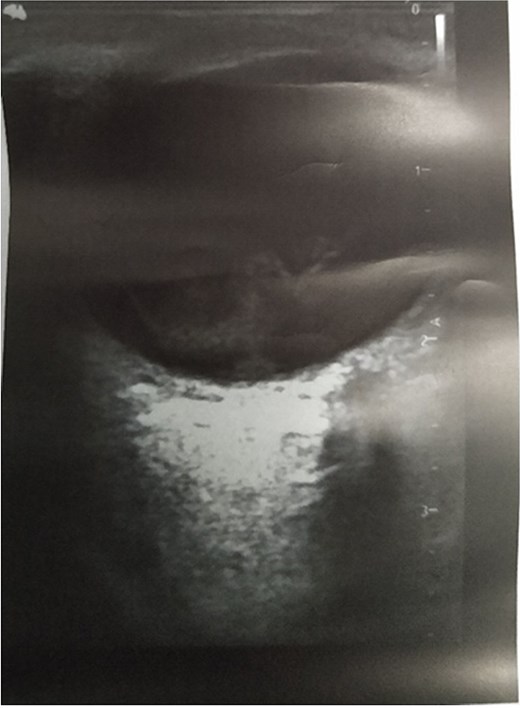

Showing ocular ultrasound of vitreous hemorrhage in the left eye.